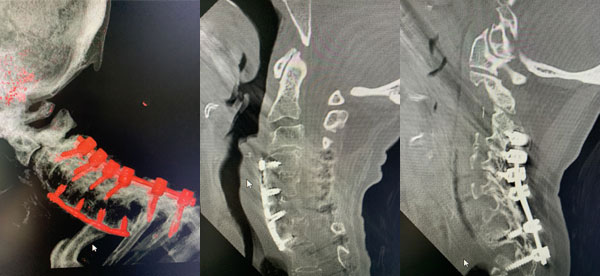

An MRI (Fig. 1) demonstrated severe stenosis at C2-3 with cord compression secondary to significant thickened posterior ligament and facet arthropathy. The patient had a posterior cervical laminectomy C1-3 to decompress the spinal cord and instrumented fusion C2-4.On exploration, the patient was deemed to be fused and the previous hardware was removed except for the lateral mass screws at C3 and C4 were left in. Postoperatively the patient had an uneventful course with some improvement in finger extensor strength.

Figures 2a, b, c: Preoperative sagittal CT scans of the cervical spine demonstrating preoperative instrumentation. Note degenerative changes and anteriolisthesis of C2 and C3.